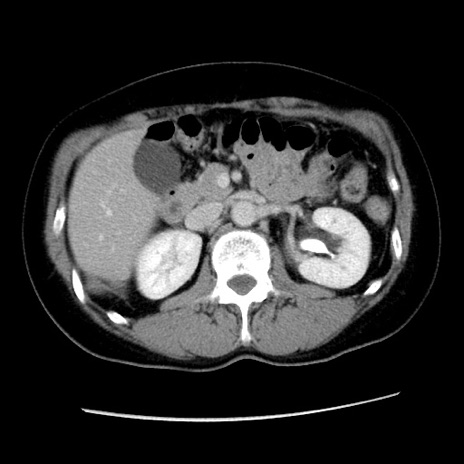

症例10(横断像)

【症例】 50歳代女性

【主訴】 腹痛

【現病歴】前日生レバーを食べた。今朝に排便あり。 昼前に突然発症の腹痛を生じ、当院救急外来を受診した。

【身体所見】 意識清明、腹部:平坦、軟、下腹部やや左を中心に圧痛・反跳痛あり、筋性防御あり

【データ】WBC 7800、CRP 0.07